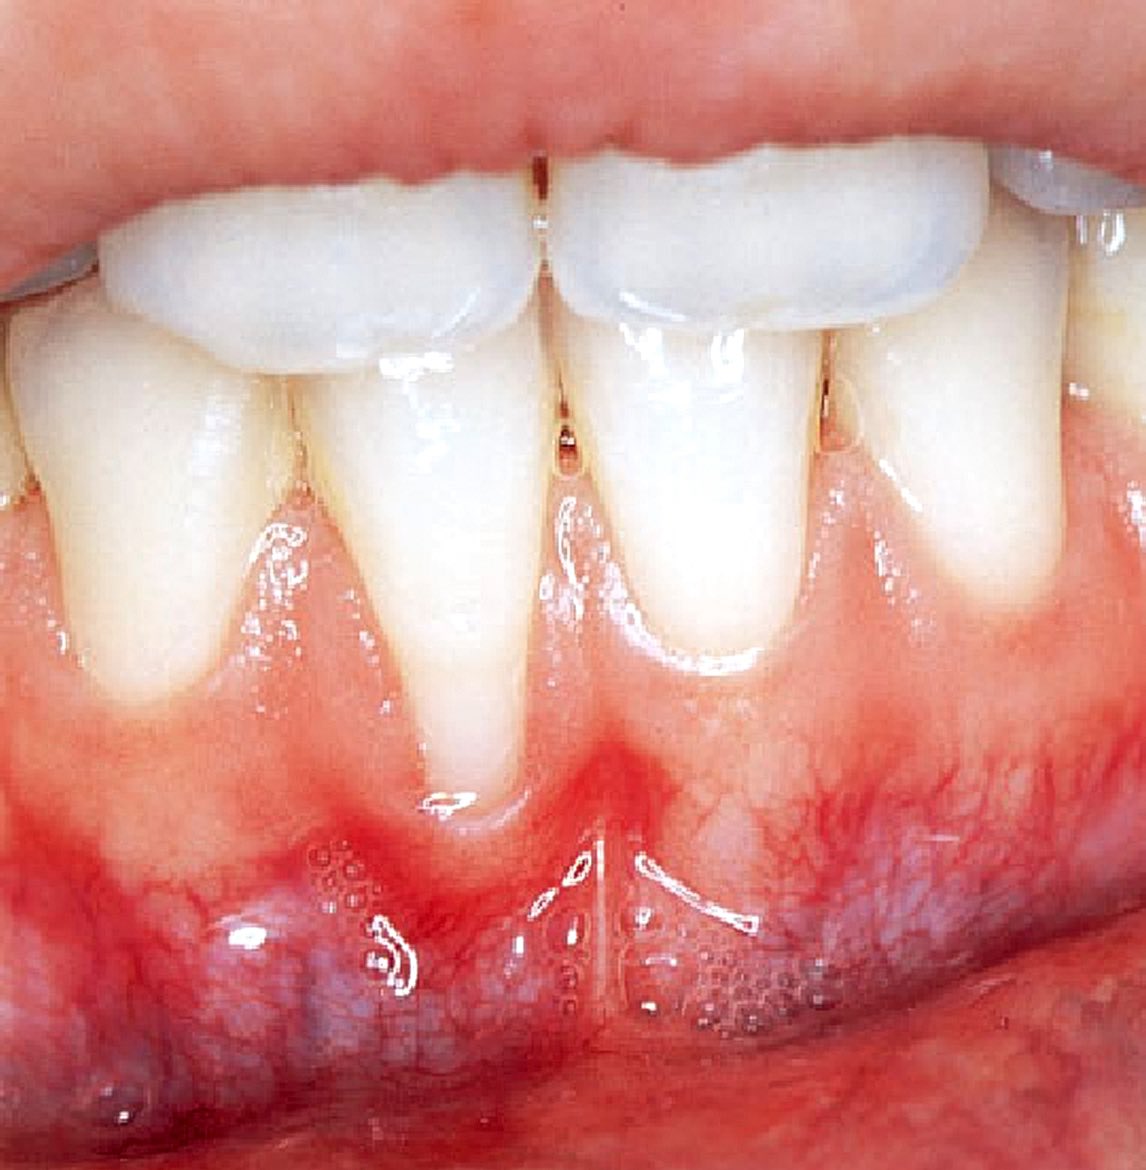

مع انتشار استعمال الحلق في منطقة الشفة واللسان.. أجد من واجبي التحذير من مضارها على المدى البعيد كإنحسار اللثة1️⃣أو تفرق الأسنان4️⃣والمدى القريب كالإلتهابات الحادة2️⃣وكسور الأسنان 3️⃣

فوجود هذه الاجسام المؤذية في مناطق دقيقة وحساسة غير مستحب